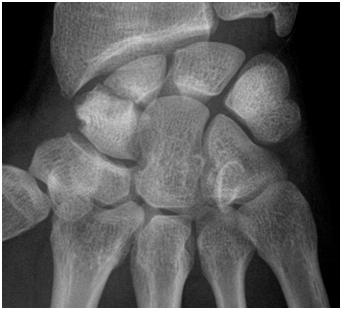

Figure 2 XR image showing scaphoid non-union.

Case report on a 21-year-old patient with scaphoid neck pseudarthrosis with three years of evolution and with an MRI that does not reveal avascular necrosis of the proximal pole (Figures 1 & 2).